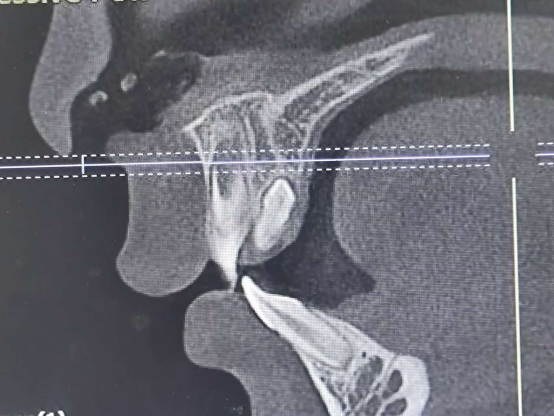

经CBCT检查,医生发现患儿上颌前牙区果然“藏”着两颗多余的多生牙。医生向家长解释道:“多生牙就像是不请自来的‘小破坏者’,虽然现在没症状,但长期留着会影响旁边正常牙齿的位置和生长,甚至可能引起更复杂的问题。”

检查可见,患儿处于替牙期,两颗正常上门牙已萌出但间距稍宽,对应腭侧的黏膜略有膨隆。为了最大程度减少患儿在治疗过程中的恐惧与不适,综合全面评估,医生最终决定在全麻下实施“上颌多生牙拔除术”。手术过程顺利,两颗“不请自来”的多生牙被精准、完整地移除。术后患儿恢复良好,家长看着孩子安稳的模样,欣慰地说道:“这下放心了,多亏处理得及时,以后换牙也不用担心被挤歪了。”